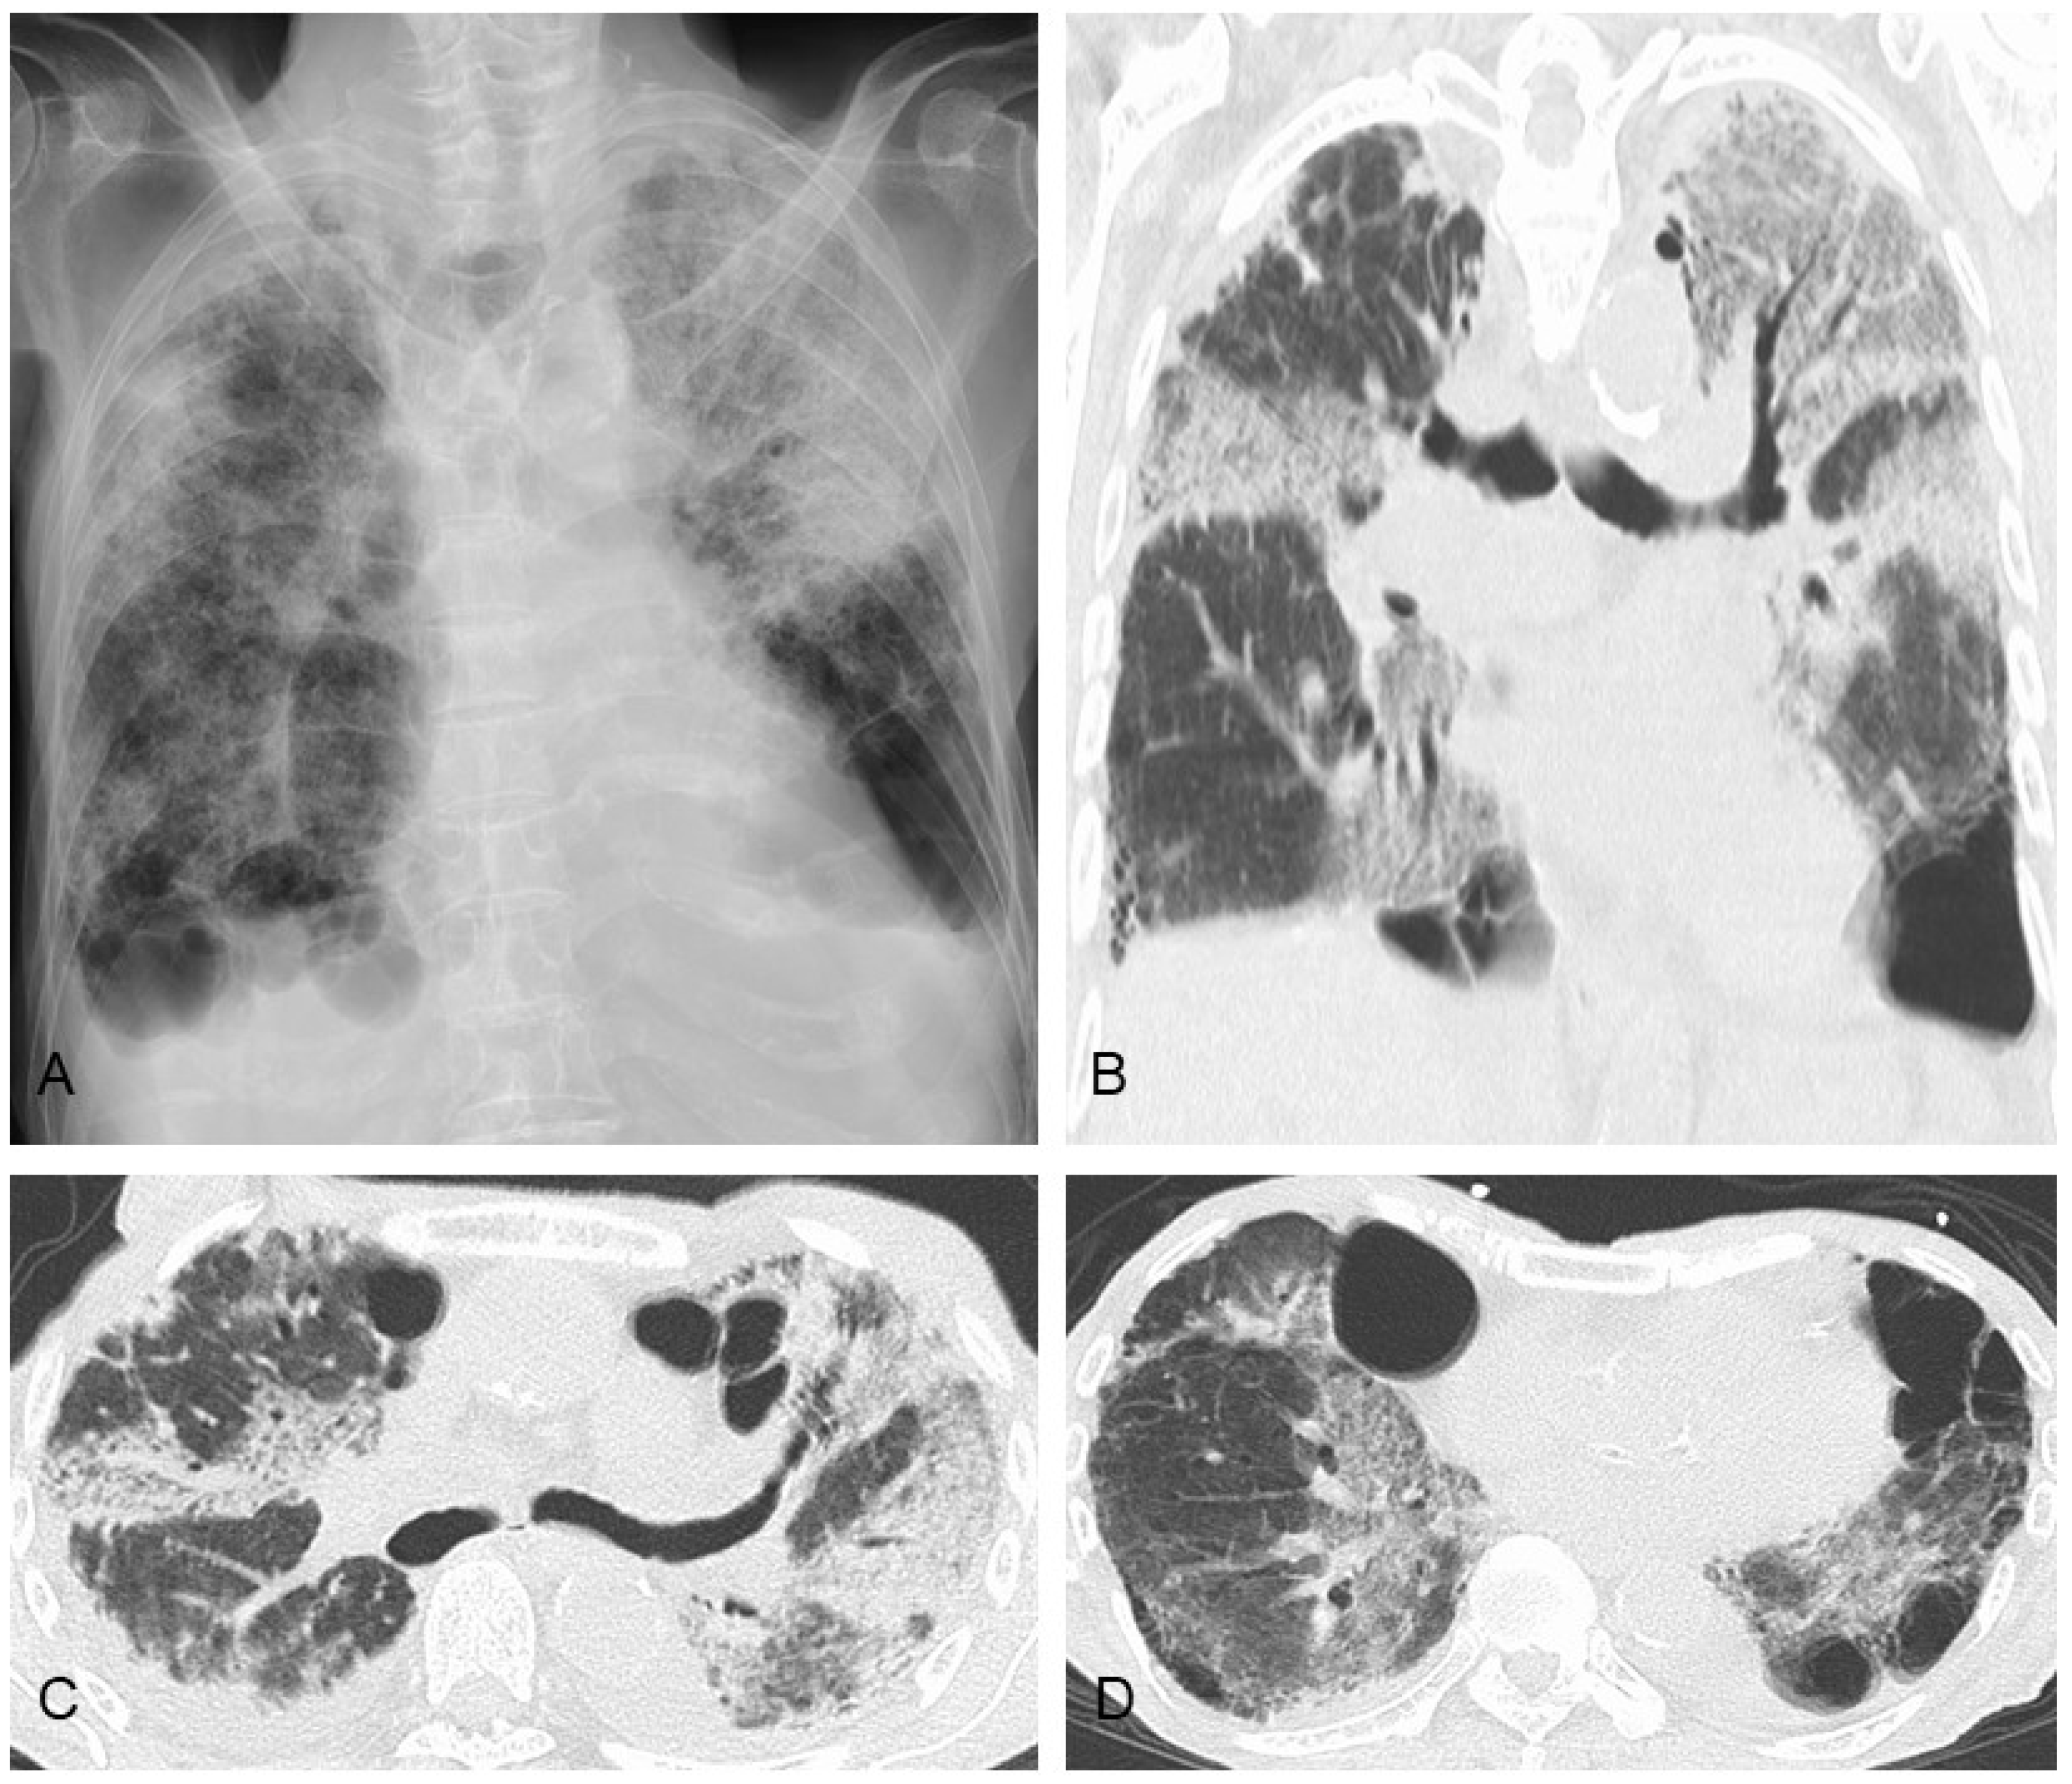

4. Secondary PPFE